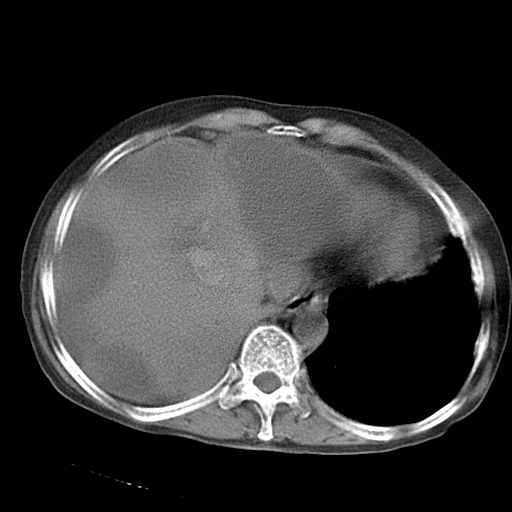

以下是引用dyqct在2006-12-7 21:08:00的发言:[br]考虑:1、肝内外胆管多发性结石伴肝左叶外侧段肝萎缩;[br] 2、右膈下多发脓肿;[br] 3、右侧少量胸腔积液、斜裂积液;[br] 4、左肾囊肿。

以下是引用jiazh在2006-12-7 20:37:00的发言:[br]肝脏周围半狐形低密度影,肝脏表面受压推移,考虑膈下脓肿可能性大;2、右侧胸腔积液

以下是引用拾荒者在2006-12-7 21:44:00的发言:[br]肝内外胆管多发结石,右膈下多发脓肿,右胸膜腔及叶间裂积液,左肾囊肿。[br] [br]